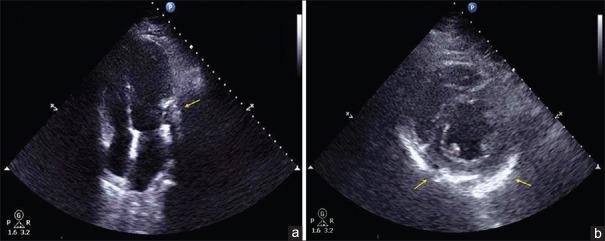

Calcific pericarditis (CP) is a rare disease which results from long-standing pericardial inflammation. Pericardial calcification may completely or partially encase the ventricles, resulting in impaired diastolic filling. We present a case of a 53-year-old male who was incidentally found to have annular CP resulting in external compression of a large territory diagonal branch (D1) reaching the apex with likely chronically occluded left anterior descending artery with collateral circulation from the right coronary artery with hemodynamic compromise on coronary angiography. This was emergently treated with a drug-eluting stent with improved D1 flow and entailed the importance of percutaneous coronary intervention as a viable option in cases of CP resulting in acute hemodynamic compromise.

钙化性心包炎(CP)是一种由长期心包炎症引起的罕见疾病。心包钙化可能完全或部分包裹心室,导致舒张期充盈受损。我们报告一例53岁男性病例,该患者偶然发现患有环形CP,导致一支到达心尖的大面积对角支(D1)受到外部压迫,左前降支可能长期闭塞,由右冠状动脉提供侧支循环,冠状动脉造影显示有血流动力学障碍。该患者紧急接受了药物洗脱支架治疗,D1血流得到改善,这表明在CP导致急性血流动力学障碍的病例中,经皮冠状动脉介入治疗是一种可行的选择。